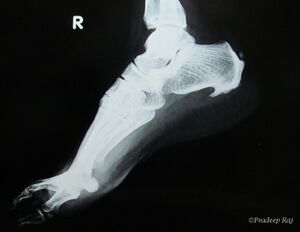

| صورة بالأشعة توضح نبتة عظمية على الجوانب الخلفية والسفلية من العقب | |